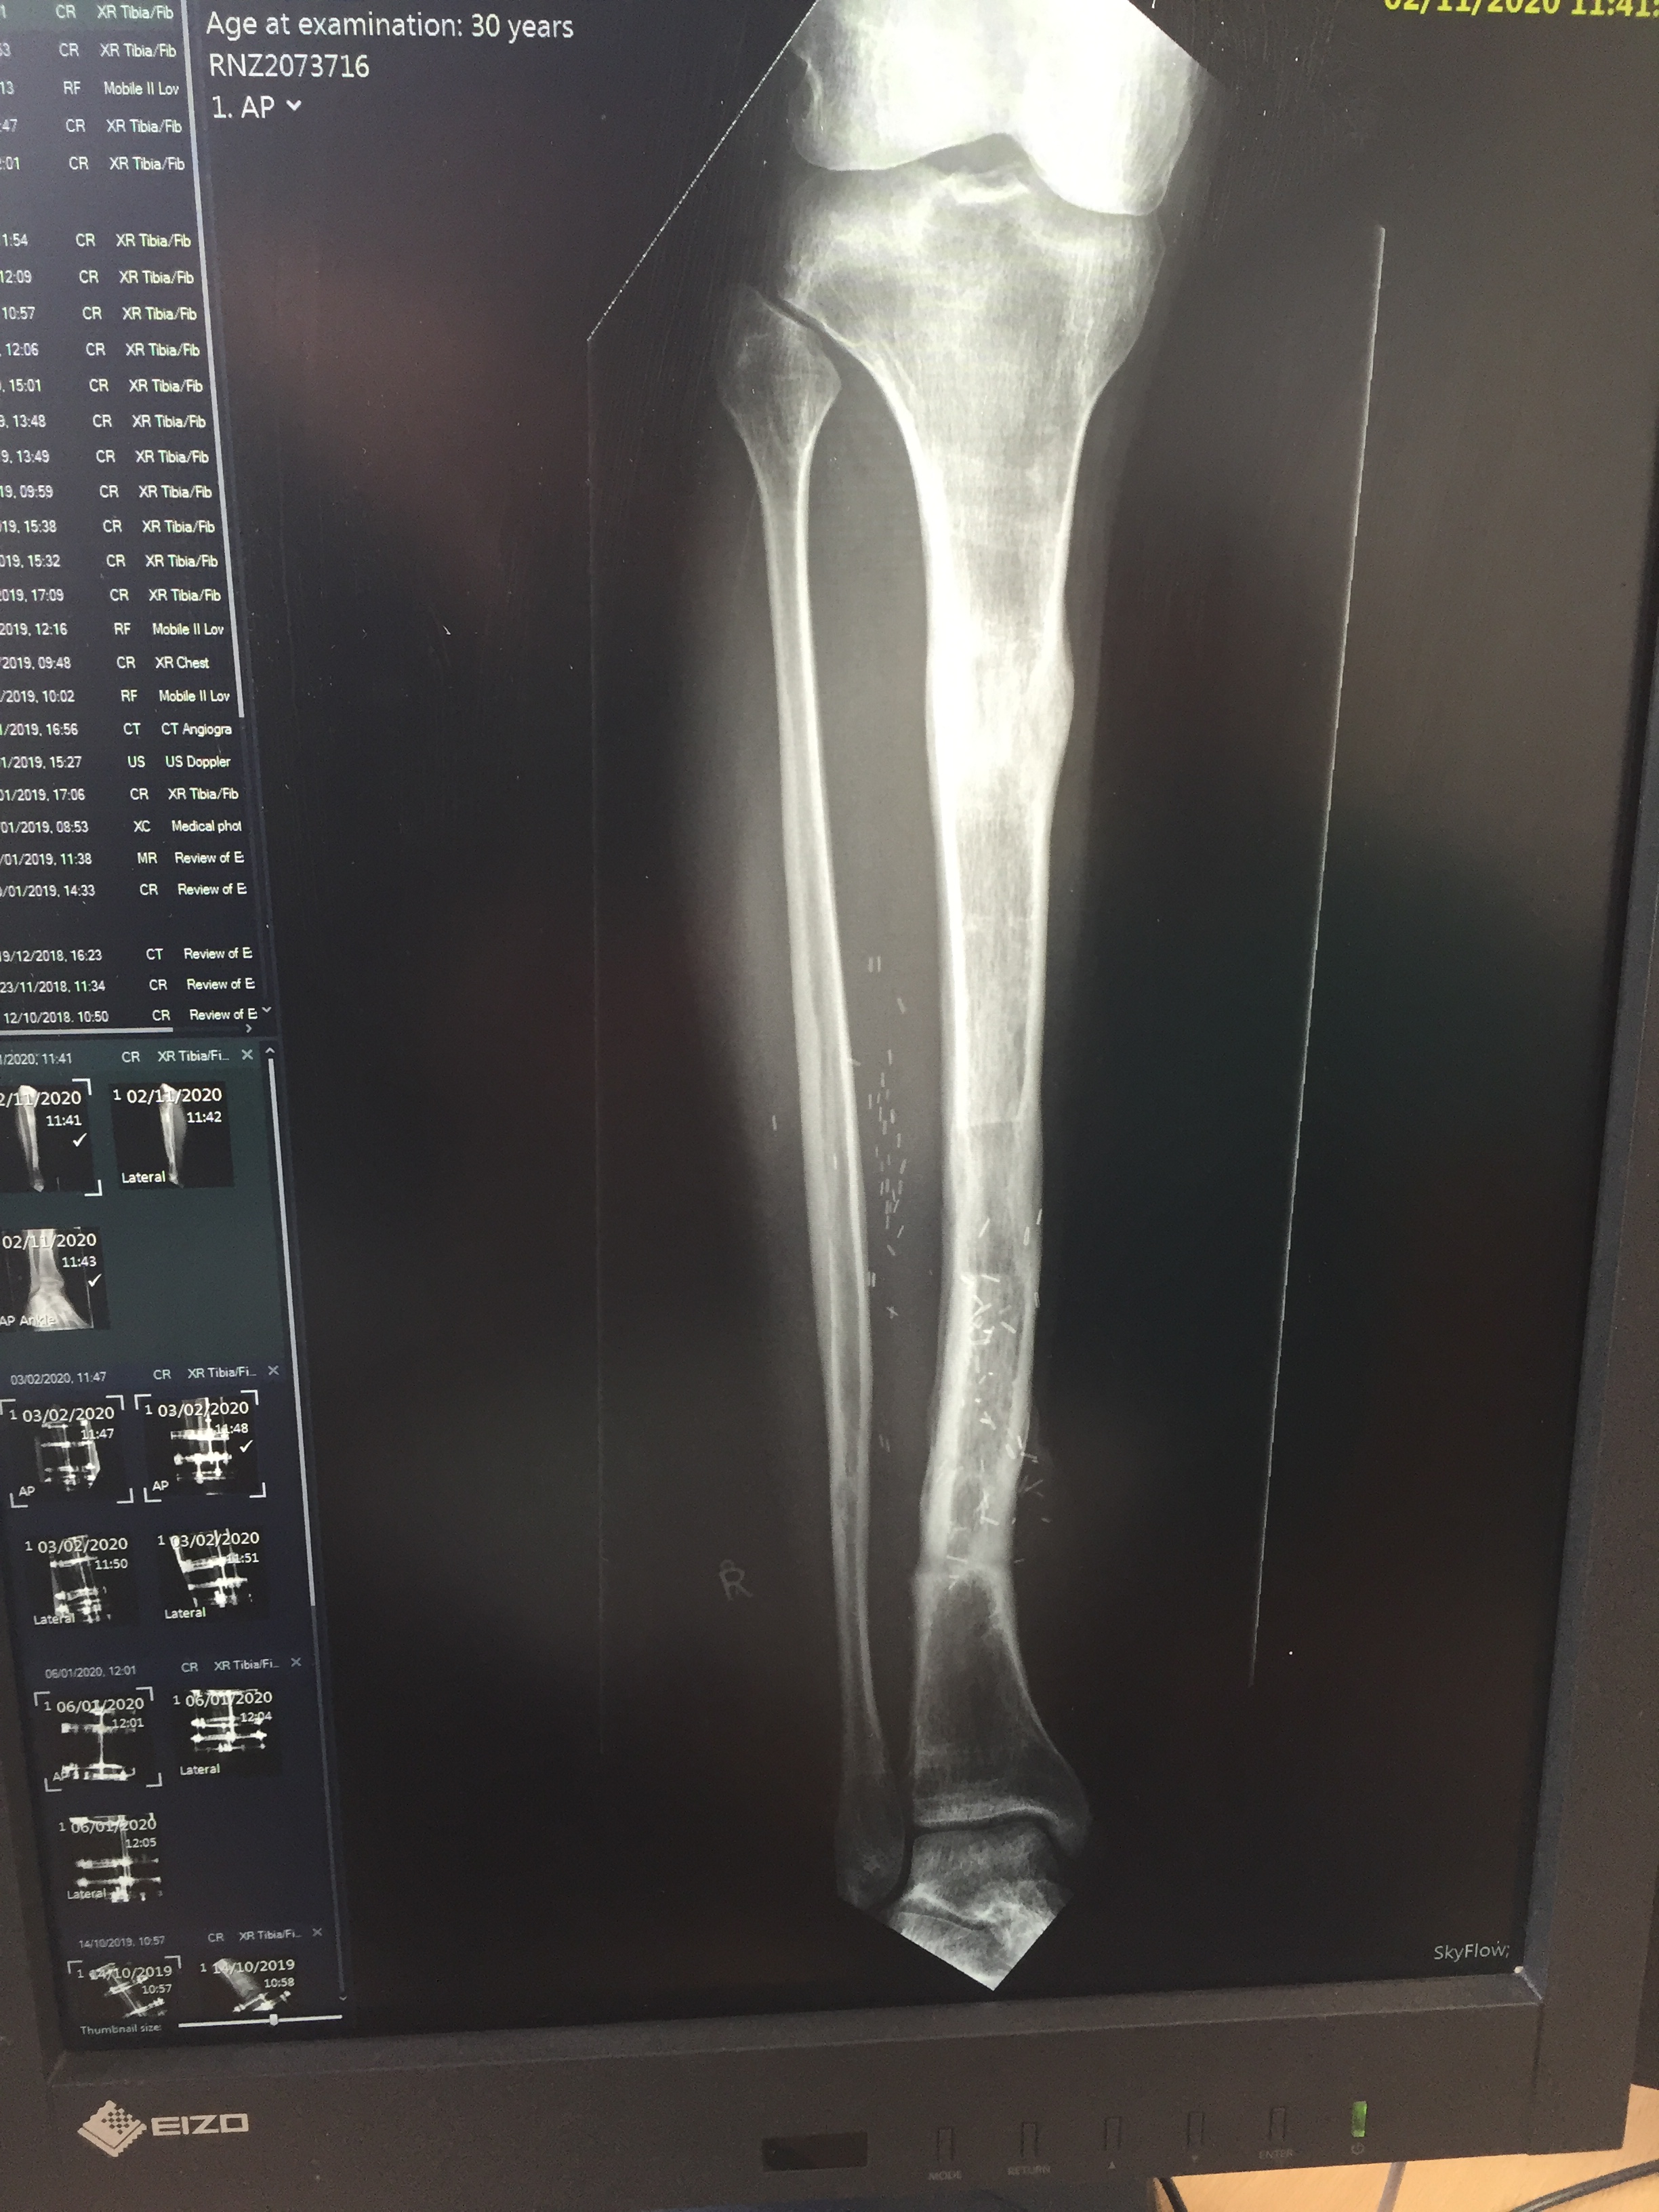

You can see in these x-Rays that the new bone was still quite soft…

IMG_1087